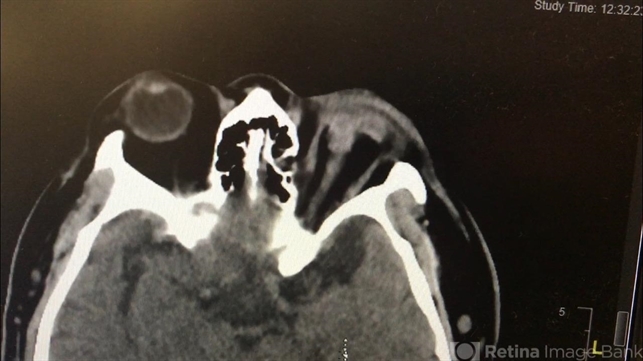

- open globe injury, CT scan

- CT Scan

- Runner meets park bench. The worst open globe I have ever seen on a CT scan. Multiple attempts at repair were made but the final visual acuity was light perception.